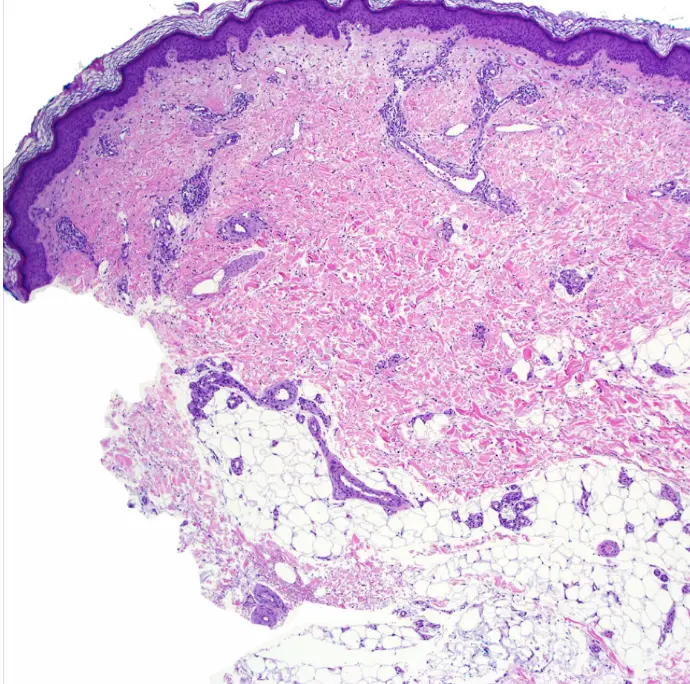

Nummular dermatitis (discoid)

What is the diagnosis?

- Nummular dermatitis (discoid).

What is the clinical presentation?

- Multiple coin-shaped eczematous plaques on the extremities and trunk.

- May be scaly but lacks the central clearing seen in tinea corporis and is KOH negative.

- Very pruritic.

- May exhibit weeping, cracking, vesicles, or crusts.

- Pathology shows spongiotic dermatitis.

What is the pathology?

- IgA.

What is the treatment?

- Clobetasol ointment.

- Emollient.